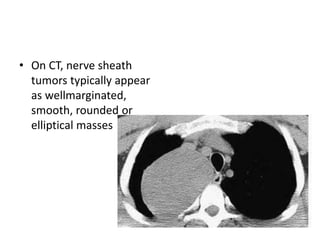

• On CT, nerve sheath

tumors typically appear

as wellmarginated,

smooth, rounded or

elliptical masses